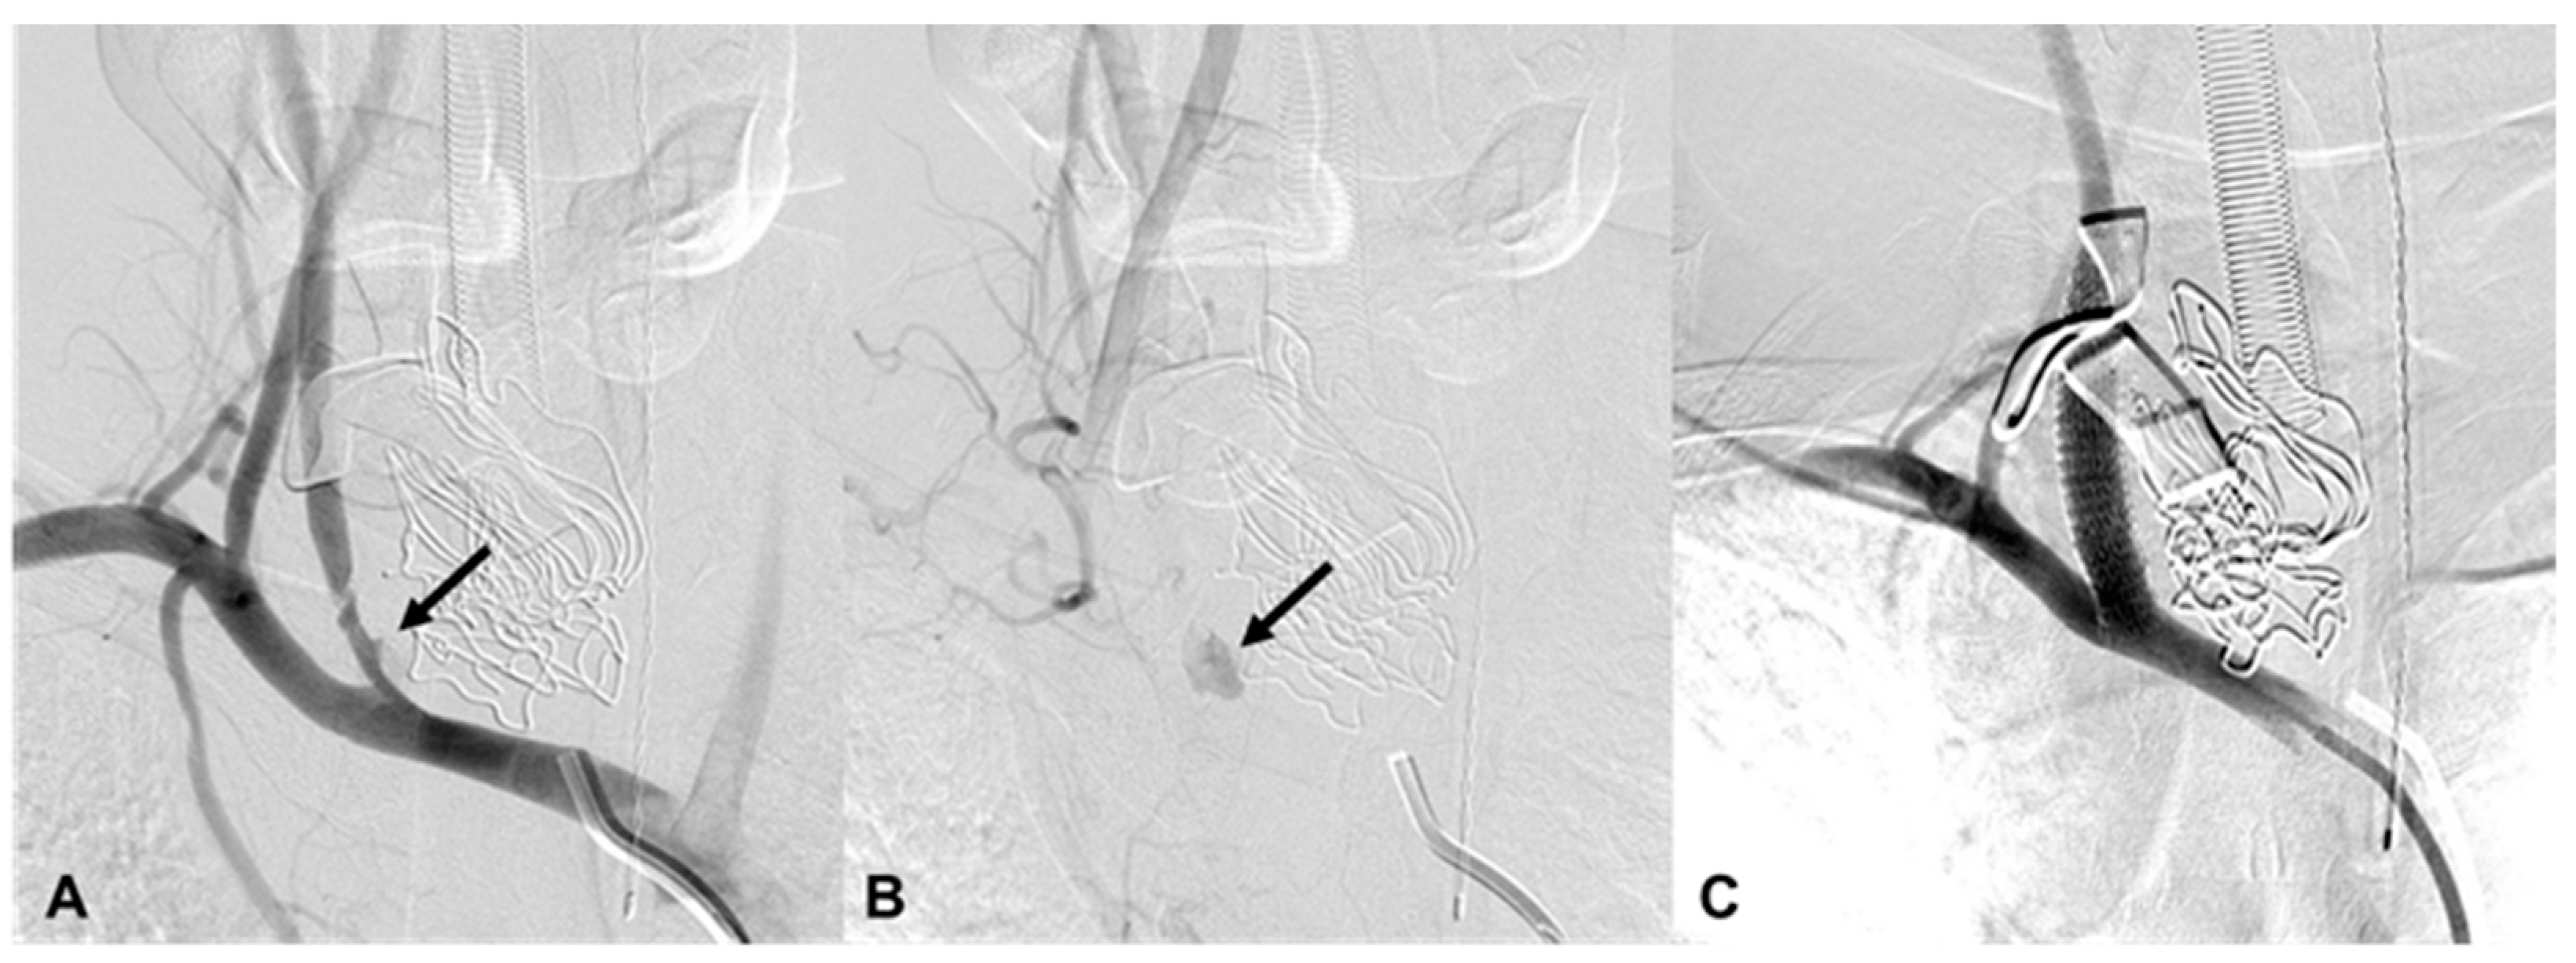

3.4. Carotid Artery Injury

| 5 | 39/M | Fall | Epistaxis | Facial and sphenoid bone fracture | EV, R IMA branch EV, R cavernous ICA (CCF) | Coil, particle | Stable 39 d F/U |

| 6 | 51/F | TA | Epistaxis and oral bleeding | Le fort I fracture | EV, R petrous ICA EV, R ascending pharyngeal | cStent, coil | Stable 423 d F/U |

| 7 | 62/M | TA | Epistaxis | Organizing hematoma, L maxillary sinus | EV, L IMA branch | Coil, glue | Death 911 d d/t esophageal cancer |

| 8 | 80/F | TA | Massive oral bleeding | Le fort II fracture | EV, L IMA branch EV, both facial | Particle, coil | Stable 651 d F/U |

| 9 | 61/M | TA | Epistaxis | Le fort II fracture | EV, L IMA branch | Coil | Stable 548 d F/U |